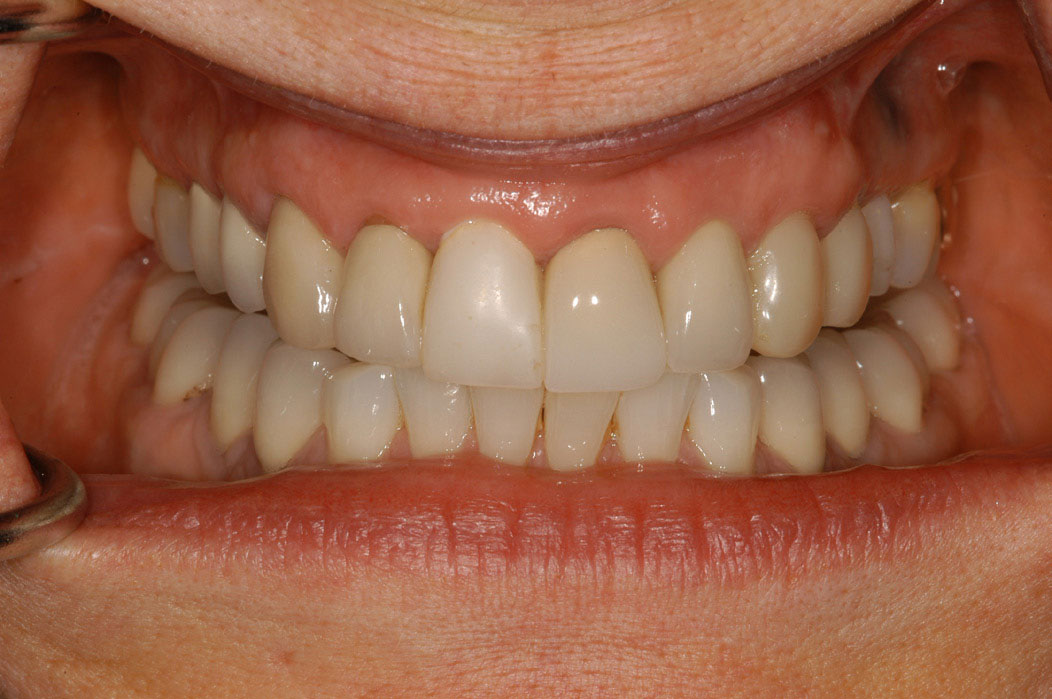

A dental implant most closely replicates natural tooth structure. Once it is osseointegrated, many patients cannot differentiate an implant from a natural tooth. Furthermore, dental implants do not decay or need root canal therapy. Even though the cost is slightly more than a bridge, it is an investment for the future, as implants usually last longer than a bridge. A 10-year report on posterior single implants shows a success rate of 97%.33 Once an implant is placed, the osseointegration and tissue healing time of approximately 4 months is necessary before a final crown is placed. A temporary crown can be placed the same day the implant is placed, but this is only for esthetics, not for function (Figure 15 through Figure 19).

Figure 15 – Extraction of anterior tooth No. 8 without detaching the gingiva.

Figure 15

Figure 16 – Extracted tooth with the root canal material (gutta percha) extending from the apex

Figure 16

Figure 17– A zircon (white) abutment was attached immediately after extraction and implant placement.

Figure 17

Figure 18 – Immediate placement of temporary crown over the abutment; laser crown lengthening was performed on the adjacent teeth to improve gingival symmetry

Figure 18

Figure 19 – Four months after surgery with temporary crown over the implant at No. 8.

Figure 19